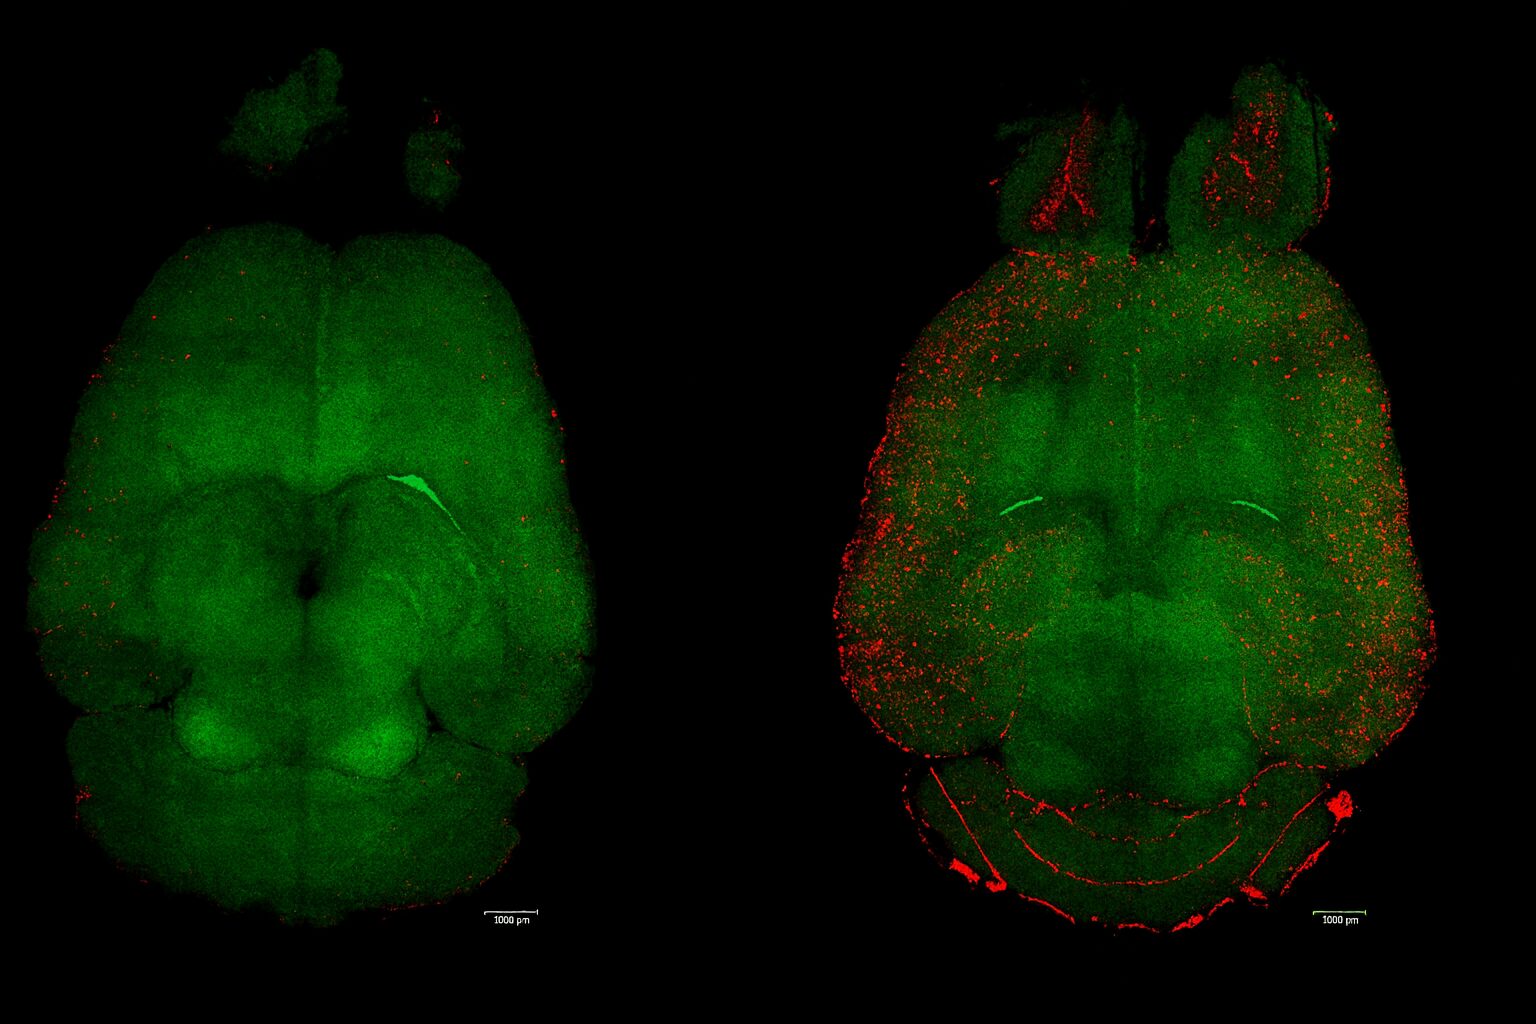

연구팀은 LRP1(Low-Density Lipoprotein Receptor-related Protein 1) 이라는 혈액뇌장벽의 핵심 분자를 모방한 나노입자를 새로 개발했다. 실험에는 유전적으로 아밀로이드β를 과다 생성하도록 조작된 쥐가 사용되었다.

이 쥐들에게 새로운 나노입자 치료제를 세 번 주사하고, 6개월 동안 행동과 뇌 활동 변화를 관찰했다.

결과는 인간 나이로 60세에 해당하는 생후 12개월의 쥐가 치료를 받고, 90세에 해당하는 18개월 시점에서 건강한 쥐와 동일한 수준의 행동 능력을 보였다.